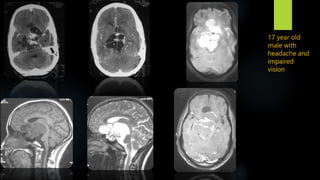

17 year old

male with

headache and

impaired

vision

• 60.

17 year old malewith headache and impaired vision